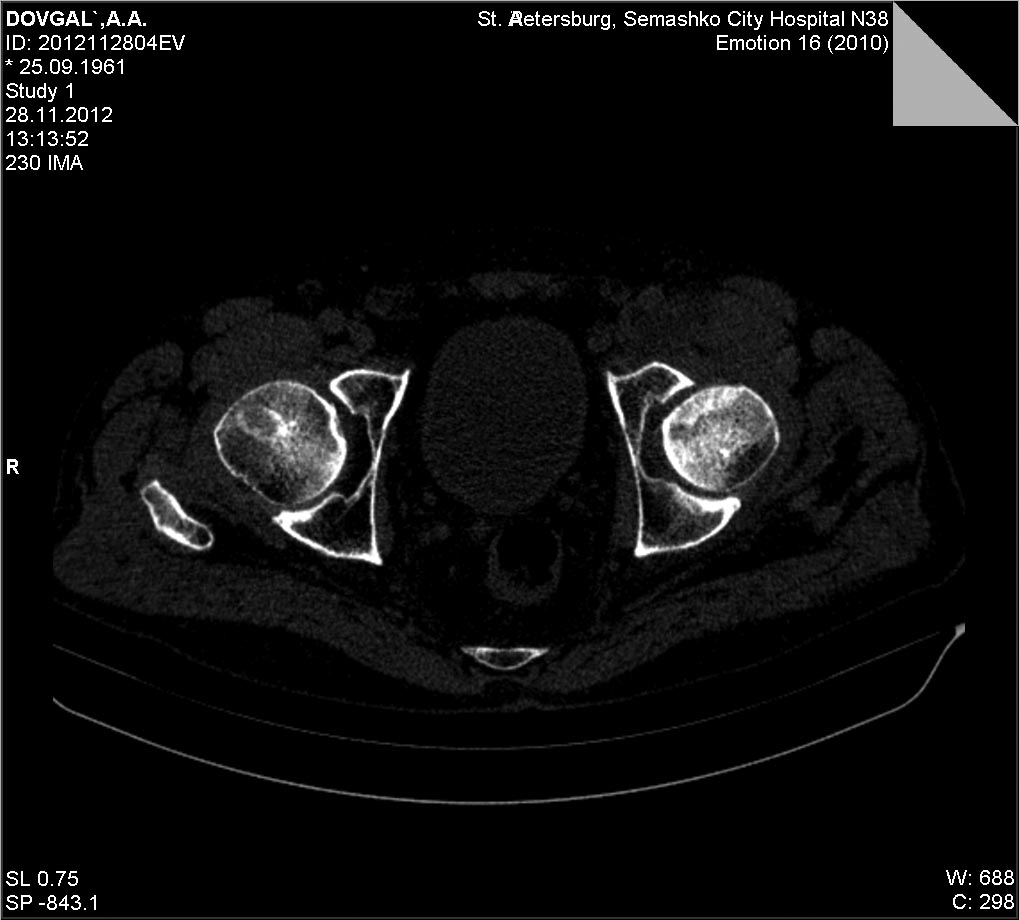

[Ortho] Импрессионный перелом головки бедренной кости

КТ

Имя     : 0601D9E1.jpg

Тип     : image/jpg

Размер  : 97769 байтов